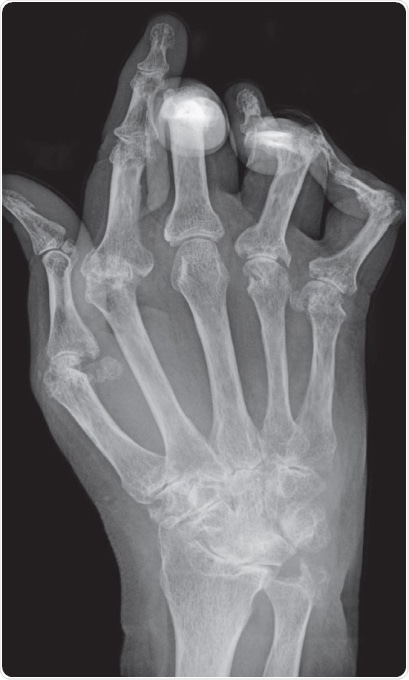

RA is a chronic destructive inflammatory disease that is distinguished by acute swelling, stiffness, and pain of the joints. Among healthy individuals, the synovial membrane, with which the joint capsule is lined, functions as a lubricant of the joint by generating synovial fluid.

The synovial membrane comprises two principle immune cell types, macrophages and synovial fibroblasts (synoviocytes), which occur within the connective tissue. However, in RA, there is an incursion of B cells, NK cells, and T cells, as well as additional chronically inflamed cell types. The synoviocytes undergo activation and permeate the surrounding cartilage, leading to cartilage degradation and bone erosion.

Furthermore, the endothelial cells in these newly constituted vessels express high levels of adhesion markers, causing multiplied inflammatory cell recruitment and infiltration. Activated CD4+ T cells express osteoprotegerin ligands, which stimulate osteoclastogenesis, while NK cells from the RA synovium similarly express increased RANKL, further stimulating osteoclastogenesis. This leads to bone erosion.

Figure 1. Typical X-ray of a hand with advanced rheumatoid arthritis. Bone erosion, cartilage degradation, and bone displacement are classic features of this disease (from Bernd Brägelmann via Wikimedia Commons)